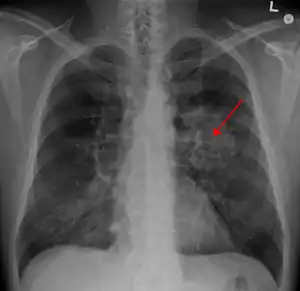

![]() Рентгенограма органів грудної порожнини: рак легені - затемнення з нерівним та нечітким контуром (позначено стрілкою). Рентгенограма органів грудної порожнини: рак легені - затемнення з нерівним та нечітким контуром (позначено стрілкою). | |

Рентгенограма грудної клітини — це один з перших кроків, які необхідно зробити, якщо пацієнт повідомляє про симптоми, які можуть вказувати на рак легень. Рентгенограма може виявити видиму пухлину, розширення середостіння (що може вказувати на поширення у лімфатичні вузли), ателектаз (колапс), консолідацію (пневмонію) або плеврит.[5] Для отримання більш докладної інформації проти тип та ступінь захворювання зазвичай використовується комп'ютерна томографія. Пробу пухлини для гістопатології зазвичай беруть за допомогою бронхоскопії або біопсії під контролем КТ.[13]

На рентгенограмі грудної клітини рак легень часто проявляється як солітарний легеневий вузол. Однак диференційна діагностика цього захворювання може зайняти багато часу. Багато інших захворювань може мати такі ж ознаки, в тому числі туберкульоз, грибкові інфекції, метастатичний рак або пневмосклероз. Менш поширеними причинами утворення солітарного легеневого вузла є гамартома, бронхогенна кіста, аденома, артеріовенозна мальформація, легенева секвестрація, ревматоїдні вузли, гранулематоз Вегенера або лімфома.[45] Рак легень можна також виявити випадково, знайшовши солітарний легеневий вузол на рентгенограмі грудної клітини або комп'ютерній томограмі, які були зроблені з інших причин.[46] Остаточний діагноз ставлять на основі гістологічного дослідження підозрілих тканин з огляду на клінічні та рентгенологічні ознаки.[3]